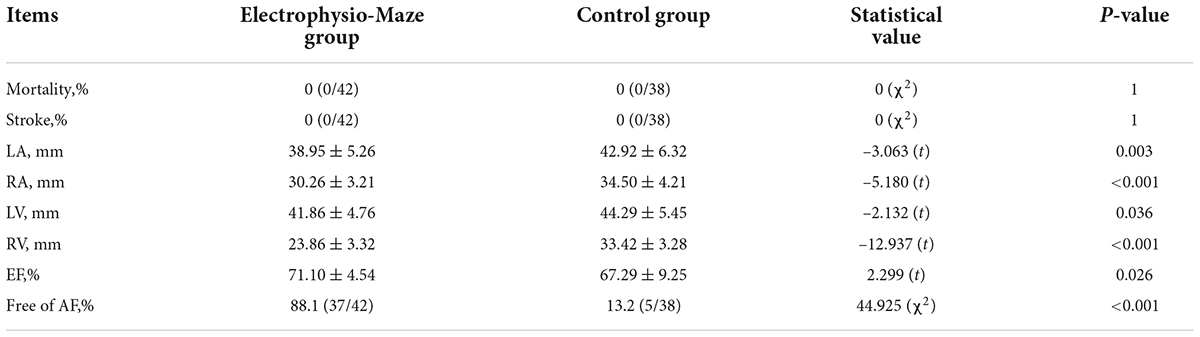

Comparison of follow-up results after 6 months between two groups

No patient died or suffered stroke during follow-up in both groups. All patients were prescribed with amiodarone for 3 months and underwent 24 h ECG Holter after 6 months. Compared with patients in the control group, patients in the Electrophysio-Maze group experienced more obvious reduction of the inner diameter of left atrium, right atrium, left ventricle, and right ventricle, a greater increase of left ventricular ejection fraction, and a higher relief from AF at 6 months (88.1 vs. 13.2%, P < 0.001, refer to Table 4).

Correlation between atrial fibrillation recurrence after 6 months and results of electrophysiological mapping in operation

There was a significant correlation between AF recurrence at 6 months both with incomplete block of ablation lines and with AF inducibility immediately after Cox-Maze IV during the operation. Additionally, AF recurrence at 6 months was correlated with a large left atrium (Table 5).